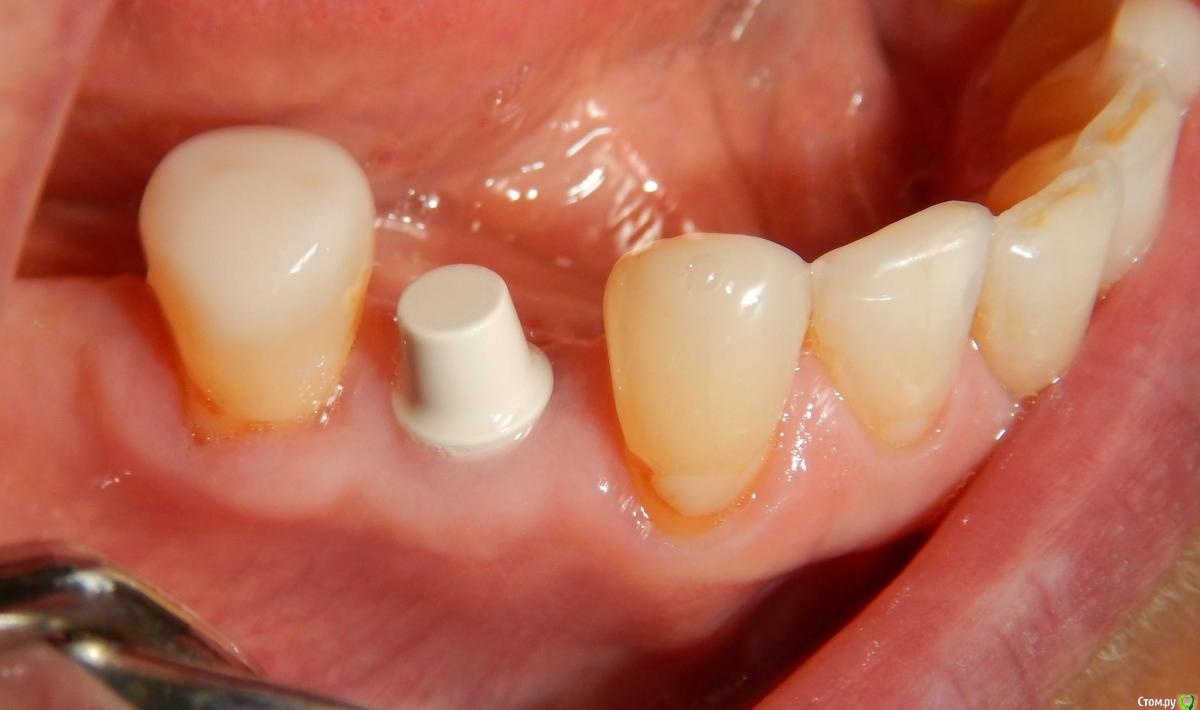

Astronaft Опубликовано 25 января, 2021 Автор Поделиться Опубликовано 25 января, 2021 Спасибо.День операции, 12 недель, день цементировки. 3 1 Ссылка на комментарий

Astronaft Опубликовано 24 января, 2021 Поделиться Опубликовано 24 января, 2021 (изменено) Одиночный цирнокиевый имплантат и расщепление без графта. Пациентка:тонкая хрупкая женщина 55 лет, сконцентрированная на своем здоровье, в некоторой мере мнительная.всегда тяжелые заживления после удалений (по опросам)есть результаты Клиффорд теста (такая книжка под 200 страниц с in vitro аллерго-пробами на все известные материалы) Поставленная цель:только цирконий Мне было интересно найти вариант найболее приемленый пациентке и мне. С минимом хирургического риска и риском сожаления пациентки про выбор костного материала. Во-первых, я не использую аллографты - философски, чужие протеины, неприятный запах - просто основываясь на своем мнении.Во-вторых, мнительные пациенты склонны "пойти и почитать" до или потом и как следствие внушить себе вещи которых может и не было. Но по скольку мысль материальна... Все обсудил заранее.План: ридж сплит (расщепление), имплантат без графта, свободный СТ графт; если случается вестибулярная рецессия - пилим зирконий во рту. Ридж сплит сделан пьезотомом - крестальный и вертикальные пропилы на глубины около 8-10мм.Пилотное сверло.Развдвинул кость остеотомами от 1.6мм до 3.5мм в диаметре.Очень мягкая кость - напомнила мегкую максиллу плотности ногтевой пластинки вестибулярно.Имплант встал легко, но торк 40нсм. СТ графт из области 18. Деэпителизирую скальпелем уже потом. Тут интересно отметить, что я перестал боятся ошметков эпителия.Пончо сверху имплантата (а-ля шашлык Карлоса).Швы. PTFE всегда хорош. 12 недель.Красивая десна.Периотест -5.8 - отличный результат.Оттиск. Циркониевая коронка симметричная другой стороне. Изменено 24 января, 2021 пользователем Astronaft 19 Ссылка на комментарий